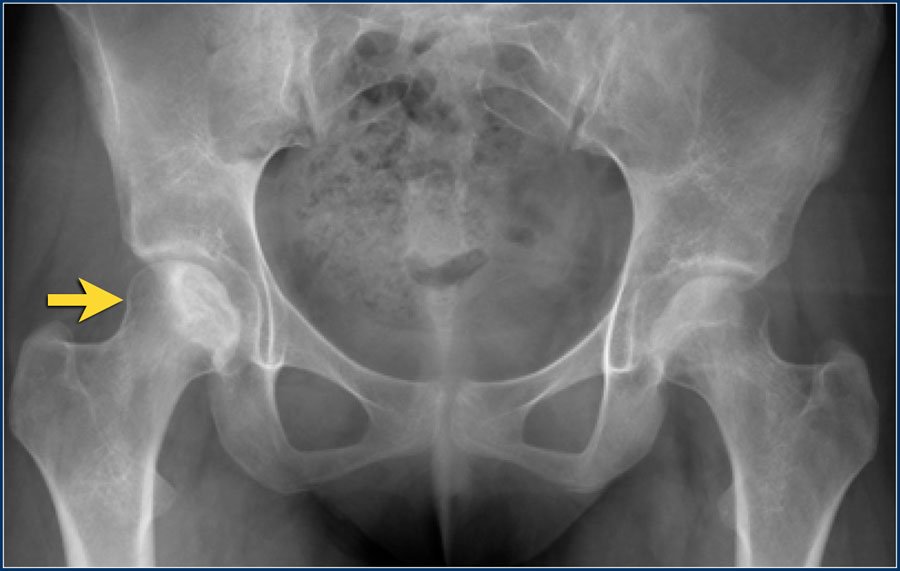

Osteonecrosis of the hip is a painful condition that occurs when the blood supply to the bone is disrupted. Because bone cells die without a blood supply, osteonecrosis can ultimately lead to destruction of the hip joint and arthritis. Osteonecrosis is also called avascular necrosis or aseptic necrosis. Although it can occur in any bone, osteonecrosis most often affects the hip. More than 20,000 people each year enter hospitals for treatment of osteonecrosis of the hip. In many cases, both hips are affected by the disease.

The hip is a ball-and-socket joint. The socket is formed by the acetabulum, which is part of the large pelvis bone. The ball is the femoral head, which is the upper end of the femur (thighbone). A slippery tissue called articular cartilage covers the surface of the ball and the socket. It creates a smooth, low friction surface that helps the bones glide easily across each other.